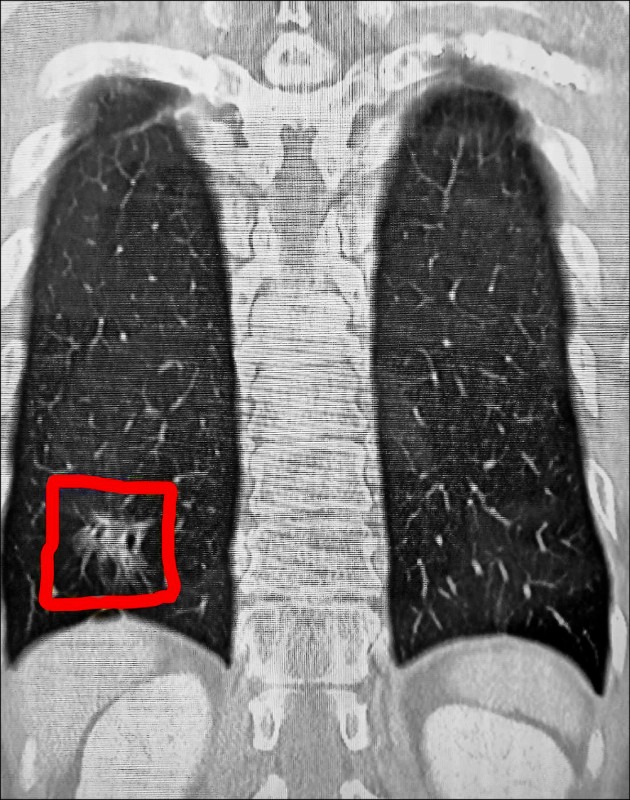

根據《TVBS新聞網》、《自由時報》報導,謝志明主任仔細分析陳先生的斷層掃描影像,赫然發現他的右下肺葉出現疑似癌症的病灶。當時陳先生的車禍傷勢在住院治療2週後就順利出院,但那塊毛玻璃樣的肺部陰影卻讓醫師相當擔憂。由於肺腺癌被稱作「隱形殺手」,早期幾乎沒有任何症狀,許多患者發現時往往已經來不及了。

3個月後陳先生回診追蹤肋骨復原狀況,謝醫師發現那處病灶依舊存在,立刻安排他接受第2次「胸腔鏡微創手術」將病灶切除。病理化驗結果證實醫師的判斷沒錯,陳先生確實罹患肺腺癌第1期。謝醫師解釋,一般胸部X光很難偵測到1公分以下的微小病變,許多肺癌病患確診時病情已經相當嚴重。